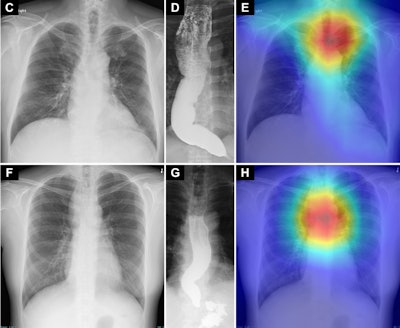

Saliency maps using Grad-CAM++ (E and H) show the model’s point of interest in chest radiographs (C and F) of patients with achalasia. The model’s point of interest is highlighted with red, yellow, and green. In both the upper and lower panels (E and H), the point of interest is located in a region around the upper esophagus that corresponds to an air esophagogram and/or air-fluid level in the esophagus in the barium esophagogram (D and G).Saliency maps using Grad-CAM++ (E and H) show the model’s point of interest in chest radiographs (C and F) of patients with achalasia. The model’s point of interest is highlighted with red, yellow, and green. In both the upper and lower panels (E and H), the point of interest is located in a region around the upper esophagus that corresponds to an air esophagogram and/or air-fluid level in the esophagus in the barium esophagogram (D and G). Osaka Metropolitan University. Image available for republishing under Creative Commons license (CC BY-NC-ND 4.0)According to the analysis, the diagnostic performance of the AI model was highly accurate, with an area under the curve of 0.964, a sensitivity of 0.941 and a specificity of 0.891. In addition, the diagnostic performance of the AI model demonstrated higher sensitivity and specificity than four physicians who reviewed the same test dataset, the researchers wrote.